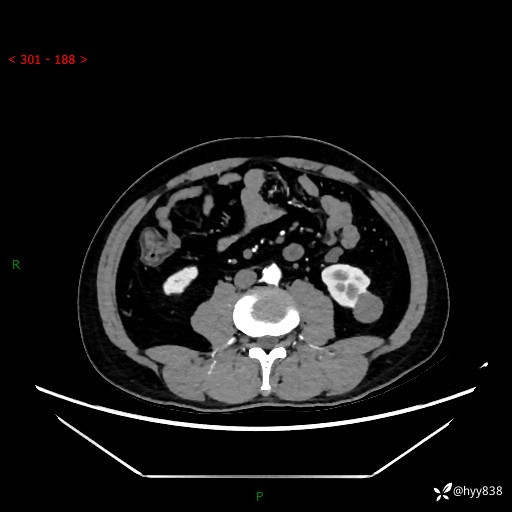

中年男性,左侧腰背部间断性胀痛不适。第一眼“乳头或囊肿”,有无意外---(有结果)

【患者信息】:41岁/男

【主诉】:左侧腰背部间断性胀痛不适1周

【现病史及既往史】:患者1周前无明显诱因出现左侧腰部疼痛,呈间断性胀痛,休息后可缓解,无放射痛,偶可见肉眼血尿,无血块,无尿频尿急尿痛,无夜尿增多,无畏寒发热、咳嗽咳痰等症状。于我院查双肾CT示:左肾占位性病变,左肾下极囊性病变,左肾轻度积水,胆囊多发结石。今为求进一步诊治来我院,门诊以“左肾占位性病变”收治入院。 起病以来,患者精神佳,饮食、睡眠良好,大便正常,小便如上诉,体力体重无明显变化。

【检查】:肾脏CT平扫+增强